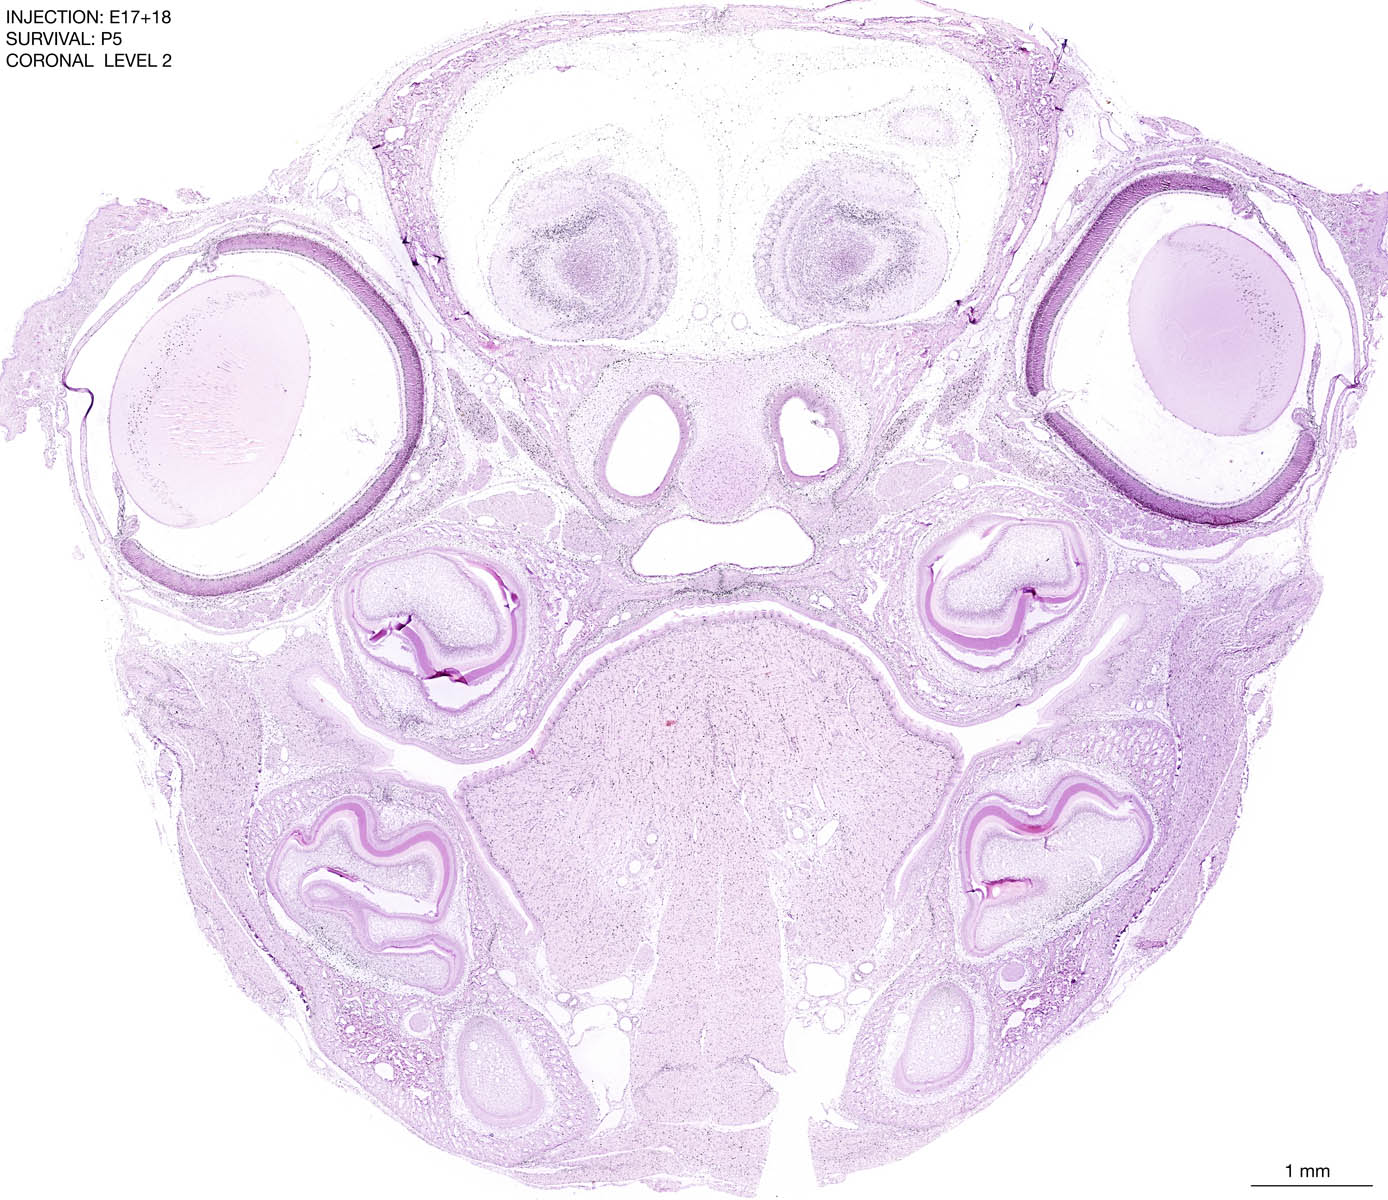

E17+18 P5 Survival The images below are from the brain of a rat that was exposed to tritiated thymidine on E17+18 and survived to P5. Download: Large | High Res Download: Large | High Res Download: Large | High Res Download: Large | High Res Download: Large | High Res Download: Large | High Res Download: Large | High Res Download: Large | High Res Download: Large | High Res Download: Large | High Res Download: Large | High Res Download: Large | High Res Download: Large | High Res Download: Large | High Res Download: Large | High Res Download: Large | High Res Download: Large | High Res Download: Large | High Res Download: Large | High Res Download: Large | High Res Download: Large | High Res Download: Large | High Res Download: Large | High Res Download: Large | High Res Download: Large | High Res Download: Large | High Res